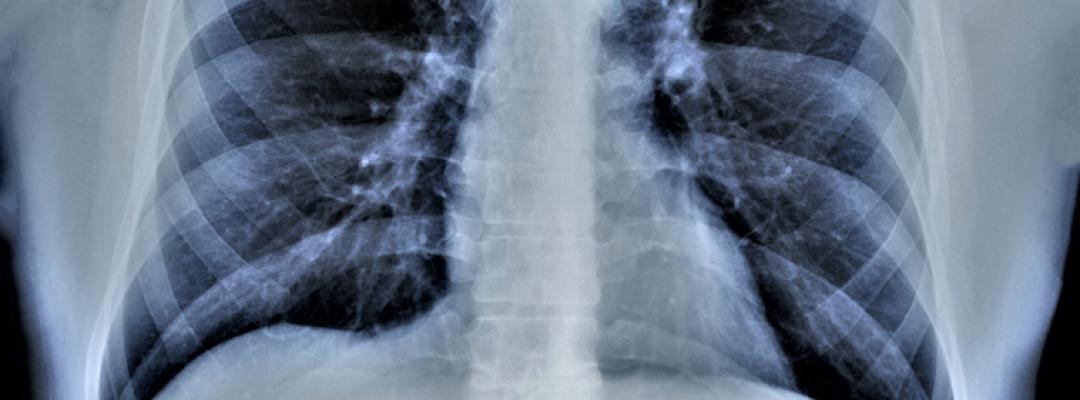

Wie funktioniert eine Lungenvolumenreduktion?Um ein fortgeschrittenes Lungenemphysem zu therapieren, kommt in vielen Fällen eine bronchoskopische Lungenvolumenreduktion (BLVR) zum Einsatz. Das überblähte Lungengewebe wird dadurch verringert und die Atmung erleichtert.

Die bronchoskopische oder endoskopische Lungenvolumenreduktion (BLVR oder ELVR) ist ein minimalinvasiver chirurgischer Eingriff, der bei einem fortgeschrittenen Lungenemphysem – einer Überblähung der Lungenbläschen (Alveolen) – zur Anwendung kommt. Das Ziel ist immer eine Verringerung des Lungenvolumens. Die „Bullektomie“ ist das operative Gegenstück zur BLVR, eine operative Entfernung von Lungenblasen.1 Heute wird jedoch der minimalinvasiven Variante der Vorzug gegeben.

Ein Bronchoskop ist jenes Instrument, mit dem eine „Lungenspiegelung“ durchgeführt werden kann, also eine Untersuchung der Lunge. Eine starre Bronchoskopie wird in Narkose durchgeführt – die Verletzungsgefahr ist höher, aber sie erlaubt umfangreichere Eingriffe. Heute wird meist eine flexible Bronchoskopie durchgeführt. Sie ist schonender, bequemer und erfordert keine Narkose. Bei einer BLVR kommen außerdem Lungenröntgen, eine Computertomografie des Brustkorbs, ein Lungenfunktionstest, ein Belastungstest, Blutabnahme, Blutgasanalyse und andere Untersuchungsmethoden zum Einsatz. Mit den Untersuchungsergebnissen kann beurteilt werden, ob und für welche Form der BLVR ein Patient infrage kommt.2 Bei Lungenvolumenreduktionen besteht auch eine Reihe von Risiken: Symptomverschlechterung (Exazerbation), Luft im Brustkorb durch Verletzung des Lungengewebes (Pneumothorax), Bluthusten oder Atemwegsinfektionen. Dem stehen jedoch große Chancen auf eine verbesserte Belastbarkeit und Lebensqualität gegenüber.3